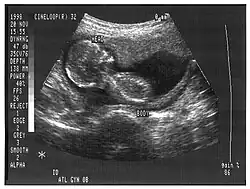

Obstetrícia e genecologia

A ecografia ginecológica examina os órgãos pélvicos femininos (especificamente o útero, os ovários e as trompas de Falópio), bem como a bexiga urinária, os anexos uterinos e a bolsa de Douglas. Utiliza transdutores concebidos para abordagens pela parede abdominal inferior, curvilíneas e sectoriais, bem como transdutores especiais, como a ecografia transvaginal.[6][7][8]

A ecografia obstétrica foi originalmente desenvolvida no final dos anos 50 e 60 por Sir Ian Donald[9][10] e é comummente utilizada durante a gravidez para verificar o desenvolvimento e a apresentação do feto. Pode ser utilizada para identificar muitas condições que podem ser potencialmente prejudiciais para a mãe e/ou para o bebé, possivelmente sem diagnóstico ou com diagnóstico tardio na ausência de ecografia. Atualmente, acredita-se que o diagnóstico tardio acarreta maior risco, se existir, associado à realização de uma ecografia. É desaconselhada a sua utilização para fins não médicos, como vídeos e fotos para "recordações" fetais.[11]

A ecografia obstétrica é utilizada principalmente para: [carece de fontes]

- Datar a gravidez (idade gestacional)

- Confirmar a viabilidade fetal

- Determinar a localização do feto, intrauterina vs ectópica

- Verificar a localização da placenta em relação ao colo do útero

- Verificar o número de fetos (gravidez múltipla)

- Verificar anormalidades físicas importantes.

- Avaliar o crescimento fetal (em busca de evidências de restrição de crescimento intrauterino (RCIU))

- Verificar os movimentos e batimentos cardíacos fetais.

- Determinar o sexo do bebé.